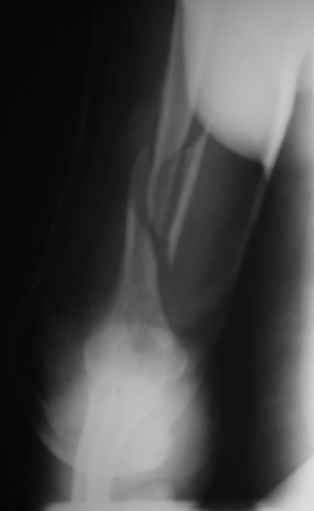

>антероградный - 30 процентов имеют боль в плече, связанную с повреждением ротаторной манжеты

Мы в последние годы все еще используем для переломов такой локализации эластичные титановые стержни (по мотивам ярославских разработок, Зверева-Ключевского). Такой стержень можно вводить не через сухожилие надостной мышцы, а дистальнее.

Снимки до, через 1 и 2 мес. после синтеза.